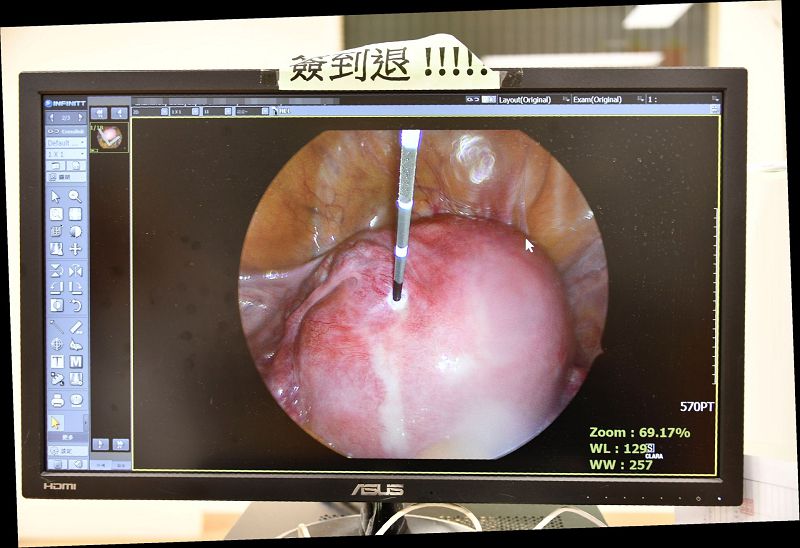

許鈞碩醫師指出,微波消融手術可透過腹部超音波導引,或腹腔鏡手術將微波消融針插入腫瘤,瞬間產生100度的熱能於腫瘤組織,搭配腹部超音波的影像協助定位,提供安全又快速的消融方式,不會有術後傷口疼痛或沾粘問題,本院至今已協助70例以上婦女解決痛經或經血量多等症狀,更提供患有子宮肌瘤或子宮肌腺瘤婦女,想保留生育功能或不想切除子宮多一項新選擇。微波消融是一種不用切開子宮且出血極少的創新治療方法,傷口小於0.2公分的針孔,不僅大幅度提高病患的生活品質,同時對身體的傷害也能降到最低,不僅術後恢復快,隔天即出院返家,一週後就能順利重回工作崗位。